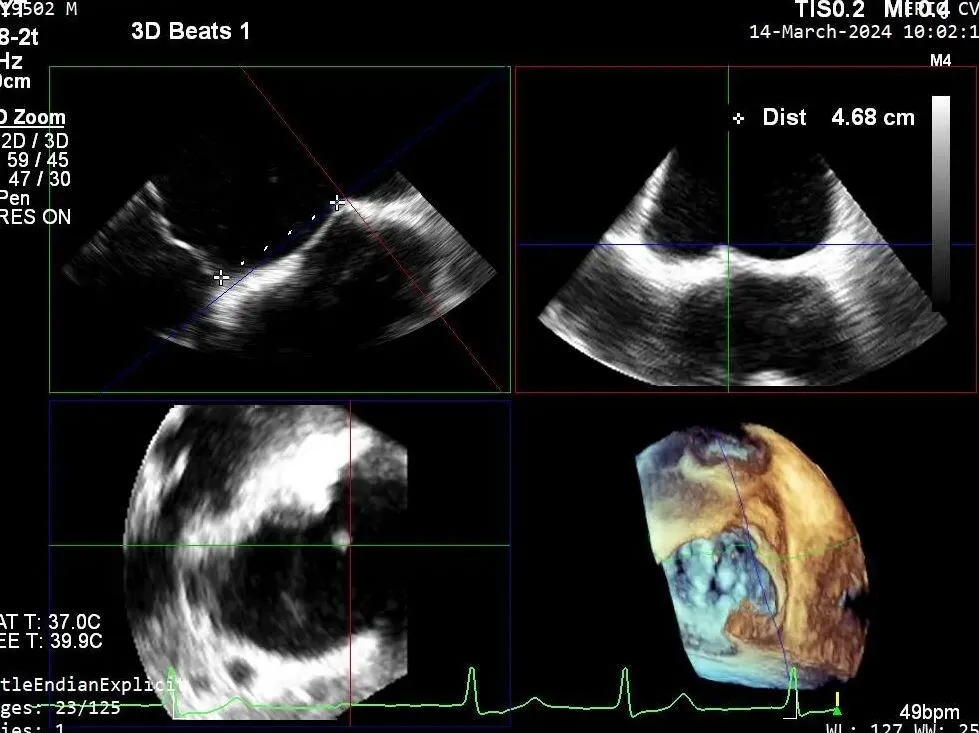

释放瓣膜夹后评估,二尖瓣呈双孔,外侧仍有残余反流

第二个瓣膜夹进入左房,调整位置及方向,紧邻第一个夹子外侧

第二个瓣膜夹释放

第二个瓣膜夹释放后评估,二尖瓣呈双孔,外侧仍有残余反流

第三个瓣膜夹进入左房,调整位置及方向,紧邻第二个夹子外侧

第三个瓣膜夹释放

第三个瓣膜夹释放后评估,释放后评估,二尖瓣呈双孔,组织桥张力合适,瓣膜夹轴向与二尖瓣闭合线垂直,无残余反流

2. 本例患者外院超声心动图考虑二尖瓣前叶脱垂,入院后经食道超声心动图明确该患者为二尖瓣后叶活动受限,呈房源性栓系,二尖瓣前叶假性脱垂,超声特征表现为心房功能性二尖瓣反流终末期,呈现出很典型的二尖瓣后瓣环向左室游离壁顶部位移和后叶挛缩表现,同时合并有明显的二尖瓣瓣环扩张、圆形化,左房增大等不利因素,术中通过精准的影像指导和手术操作,成功行TEER,二尖瓣反流程度减轻至微量。